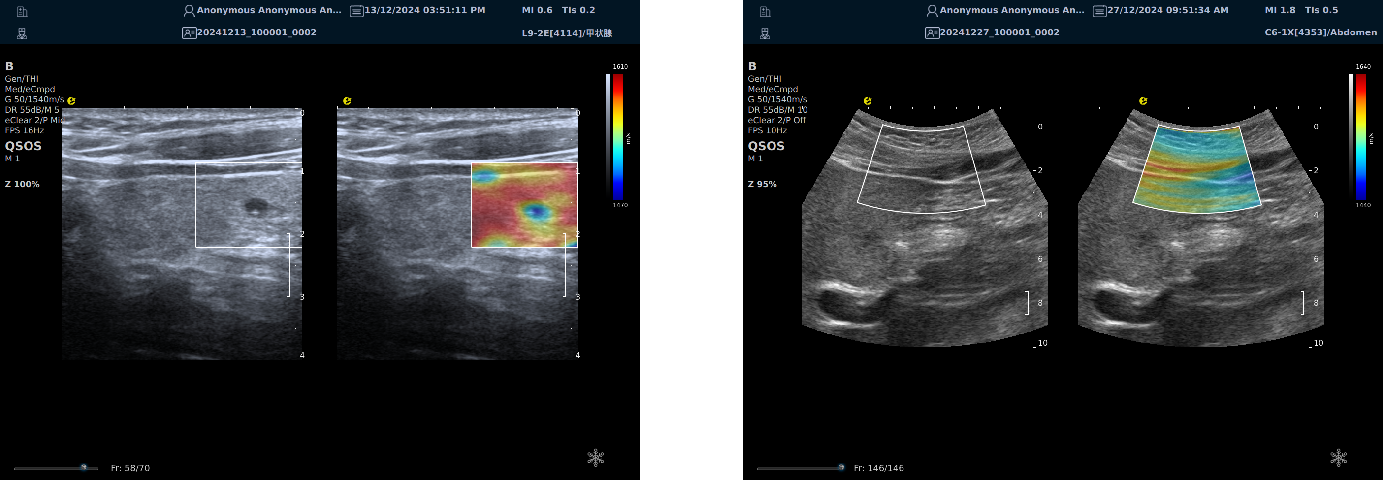

声速定量成像

作为一种新兴的超声成像技术,为医学诊断和生物医学研究提供了重要的信息。利用声波在不同组织中的传播速度差异,测量每个部位的声速,并将测出来的声速通过彩色编码进行显示,生成反映组织物理特性的图像(即声速成像图),对于疾病的早期检测、诊断和治疗评估具有重要的意义。

声速定量成像给临床提供了全新的诊疗思路及工具。

image.png